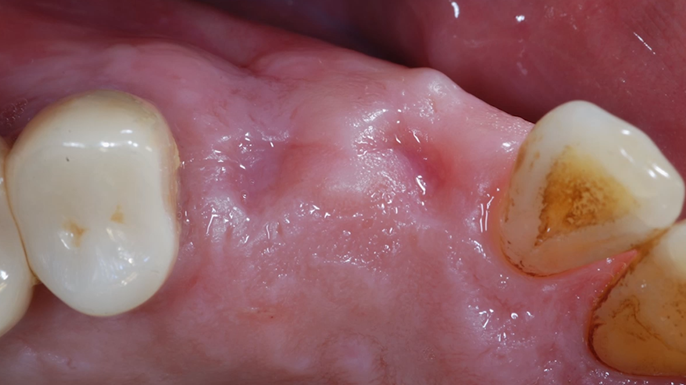

“Prefabricated provisional restorations can serve as custom healing abutments in case of insufficient initial stability for one-day implants. ”

Clinical case: Immediate implant placement using R2GATE Guide & custom healing abutment

- Courtesy of Dr. Sam Omar, Egypt -

Dr. Dr. Sam Omar,Digital Guided Surgery,Digital Digital Guided Surgery,Digital ONE-DAY Implant,Maxillary Posterior,#16,Guided surgery,Loading,Flapless,AnyRidge,R2GATE,MEGA ISQ,R2GATE Full surgical kit

Implant system-AnyRidge, R2 Guide, R2GATE Full Surgical Kit, Mega ISQ,